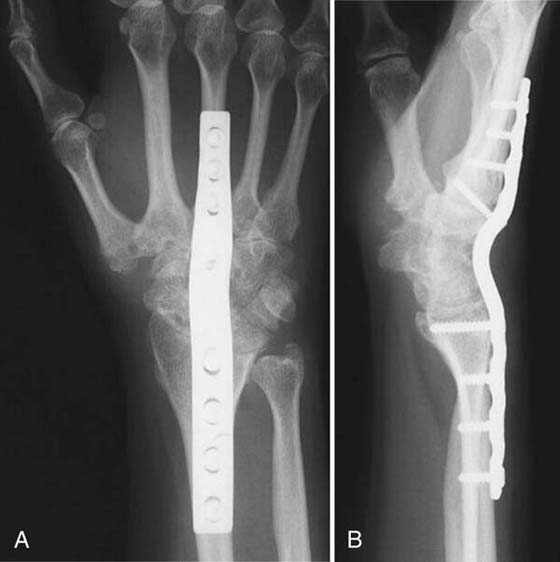

The results of fusion by the AO method with plate fixation (Fig. 76-10) and local bone graft are consistently good, with minimal nonunion and good pain relief.5,54,55 Complications include plate tenderness in 19%, extensor tendon adhesions requiring tenolysis in 3.5%, carpal tunnel syndrome in 4% to 10%, and distal radioulnar joint pain in up to 3.5%.

images

Figure 76-10 Total wrist arthrodesis using an AO wrist fusion plate.